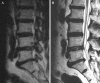

The objective of the study was to demonstrate the clinical characteristics of dural tears during percutaneous endoscopic lumbar discectomy (PELD) and to discuss how to prevent this unintended complication. The study used data from 816 consecutive patients who underwent PELD between 2003 and 2007. A total of nine patients (1.1%) experienced symptomatic dural tears. The clinical outcomes were evaluated using the visual analogue scale (VAS), the Oswestry disability index (ODI), and modified MacNab criteria. Intractable radicular pain was the most common symptom, while classical manifestations, such as CSF leakage or wound swelling, were rare. In three of the nine cases, the dural tears were detected intraoperatively, while the remaining six cases were not recognized during the procedure. Among the unrecognized patients, two patients were found with nerve root herniation causing profound neurological deficits. All patients were managed by secondary open repair surgeries. The mean follow-up period was 30.8 months. The mean VAS of radicular leg pain improved from 8.3 to 2.6, and that of back pain improved from 4.1 to 2.6. The mean ODI improved from 69.6 to 29.2%. The final outcomes were excellent in one, good in five, fair in one, and poor in two patients. As application of the endoscopic procedure has been broadened to more complex cases, the risk of dural tears may increase. Unrecognized dural tear with nerve root herniation may cause permanent neurological sequelae. Accurate information and proper technical considerations are essential to prevent this unpredictable complication.